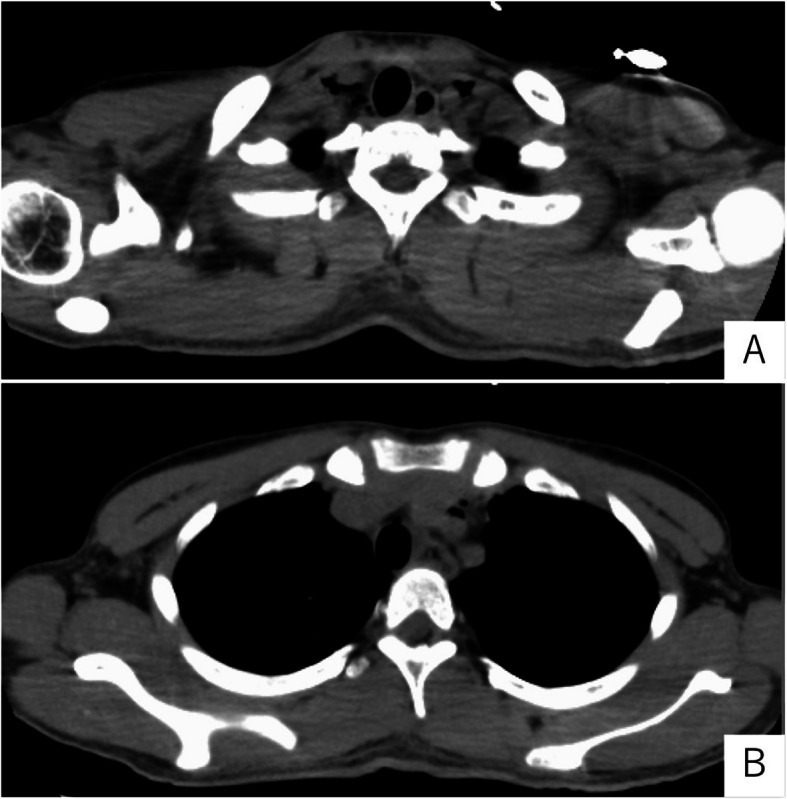

Case presentation: A 20-year-old foreign technical intern visited to a hospital because of nausea and shortness of breath. He had been diagnosed with diabetes in his home country and had initiated insulin therapy; however, since arriving in Japan, he had not accessed any medical services. Computed tomography revealed pneumomediastinum, while laboratory tests showed marked hyperglycemia, metabolic acidosis, and a significantly elevated blood ketone level (15,044 µmol/L). The patient was diagnosed with Hamman's syndrome associated with DKA. Upper gastrointestinal endoscopy showed no evidence of gastrointestinal perforation. Conservative intensive care, including insulin therapy and fluid resuscitation, resulted in clinical improvement.